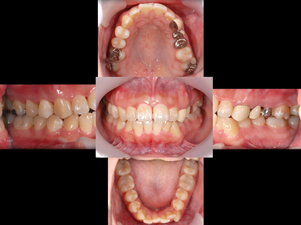

症例3(再生療法)

Before

After

- POINT

- 他院で歯周病の治療をしていましたが、なかなか歯周病が改善されず、セカンドオピニオンにて来院された患者様です。歯周病の進行した部分に再生療法を行い(エムドゲインを使った歯茎の手術)ホームケアを徹底することで改善されました。

今後も継続したメインテナンスが必要です。